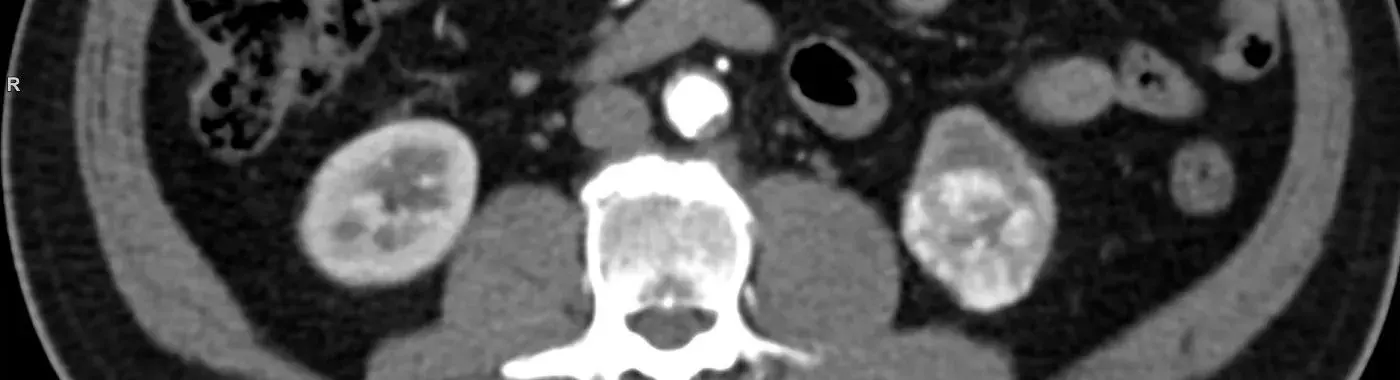

• CT (Computed Tomography) Scan: A CT scan provides detailed, cross-sectional images of the abdomen and chest. It can help doctors see the exact size of the tumor, whether it has spread to nearby structures, and whether it has spread to the lungs.